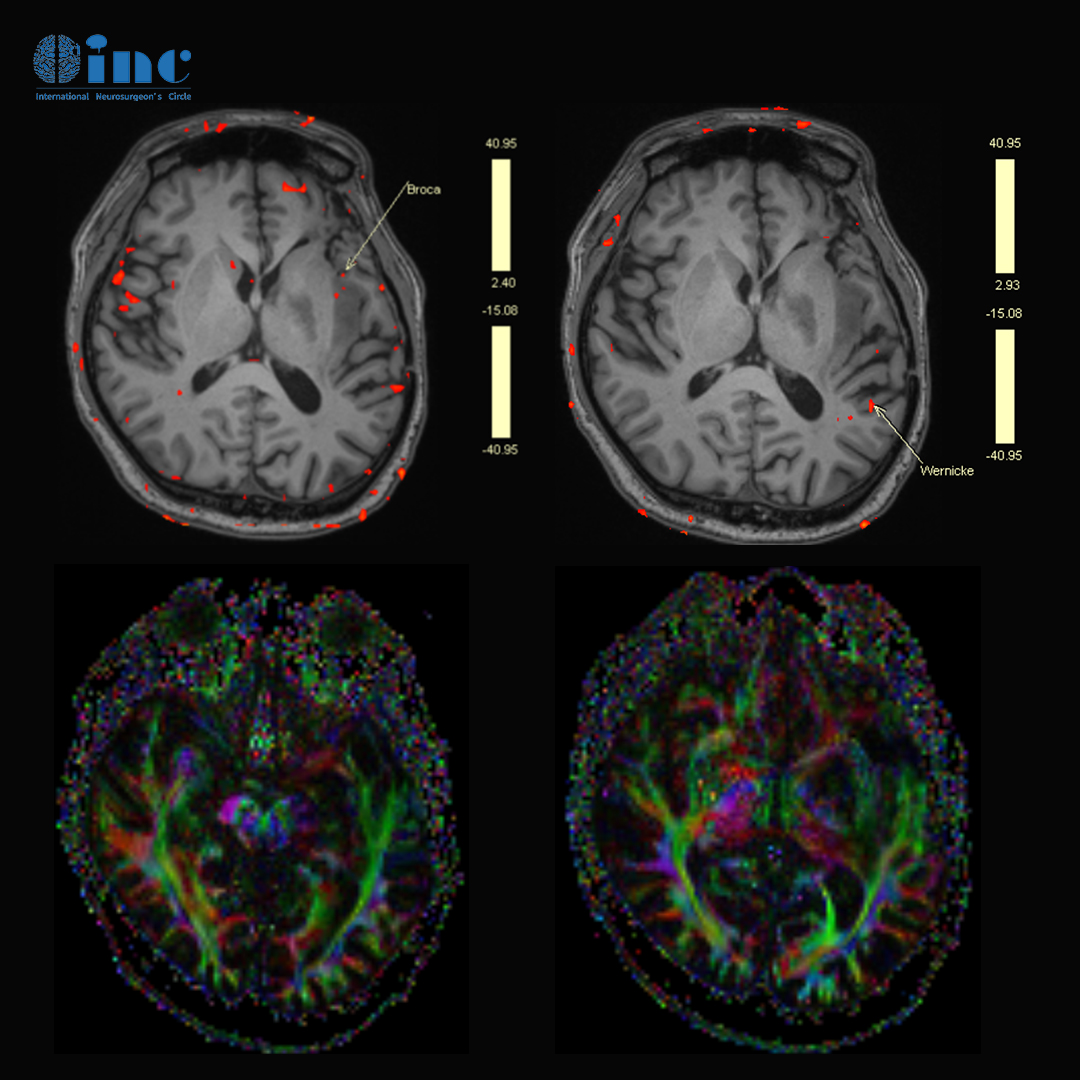

手術(shù)前,通過功能核磁和DTI成像判斷患者語言功能區(qū)和重要的神經(jīng)纖維束